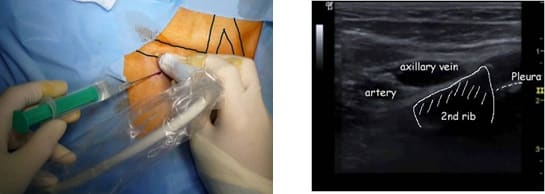

3. Acceso por la vena subclavia en adultos

La vía subclavia en comparación la vía yugular es más funcional y estética evitando muchas de las complicaciones relacionadas con la punción a ciegas.

Además, no es necesario tunelizar, es un abordaje más cómodo et rápido.

Hoy en día, nuestra vía de abordaje de elección era la vena subclavia en el surco deltopectoral, lo cual permite una gran discreción para los pacientes (respeto del escote). Colocamos el 99% de nuestros puertos con este abordaje.

Se han realizado alrededor de 10.000 procedimientos en nuestro instituto desde 2007, con esta técnica y con esta técnica no hubo casos de neumotórax, punción arterial o síndrome de Pinch off.

Se punciona la vena en el fondo del bolsillo: de esta manera el catéter tiene un recorrido más fisiológico y evitamos los posibles curvas o acodamientos que pueden crearse cuando la vena se punciona desde otro lugar.